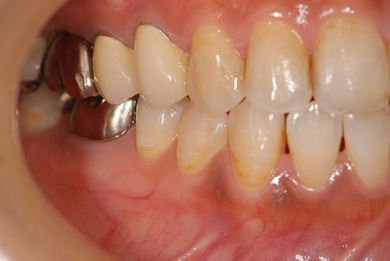

抜歯即日スピードインプラント治療

| 性別/年齢 | 女性 / 39歳 | ||||||||||||||||||||||||||||||||

| 主訴 | 左前歯の虫歯治療を希望。 | ||||||||||||||||||||||||||||||||

| 治療内容 | インプラント1本(抜歯即日スピードインプラント)、メタルボンドセラミック1本 | ||||||||||||||||||||||||||||||||

| 総治療費 | 458,588円 | ||||||||||||||||||||||||||||||||

| 治療期間 | 1年0ヶ月 |